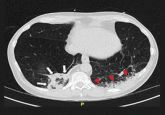

An intravenous drug user with persistent dyspnea and lung infiltrates